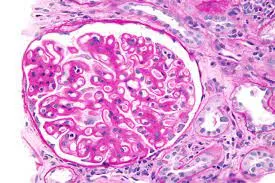

Injúria Renal Aguda (revisão Lancet 2025)

Injúria Renal Aguda (revisão Lancet 2025)